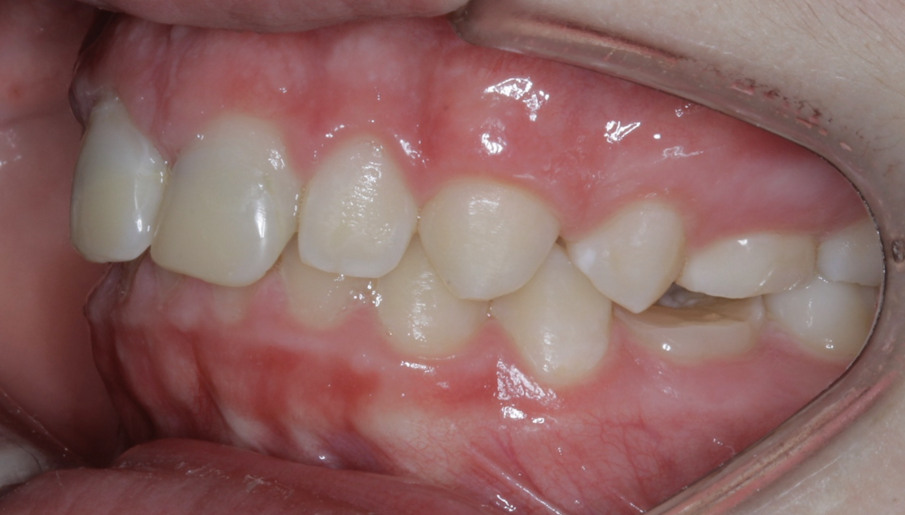

The anterior gummy smile The anterior gummy smile is one in which the patient shows excess gingival display from maxillary canine to maxillary canine (Figs. 4 & 5, beginning of treatment). This takes into account the ideal crown shape and size, where the patient has true anterior maxillary excess and is not just in need of a gingivectomy or crown lengthening procedure. To best determine if gummy smile treatment is needed in the anterior, the authentic smile photograph is used, alongside measurement of the incisor display at rest. If the resting incisor display is greater than threequarters in the adult patient without altered passive eruption, gummy smile treatment is needed. These cases are treated using two TADs placed between tooth #13 and #12 or between #22 and #23 using a 1.6 × 6.0 mm TAD. If slight posterior impaction is desired, bite turbos with Triad Gel (Dentsply Sirona) are placed on teeth #37 and #47 and squeezing exercises used to impact posterior molars engaging the posterior fibres of the temporal muscles (60 squeezes six times per day).